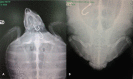

It has been estimated that 44,000 Caretta caretta turtles die every year due to anthropomorphic activity in the Mediterranean Sea, and that longline fishing is one of the most significant causes of mortality. A total of 482 specimens of C. caretta were rescued from different parts of the Sicilian coast (Mediterranean Sea) from 2014 to 2016. The most numerous stranding was recorded during the spring and summer seasons, mainly along the north and eastern coasts of Sicily. The curved carapace length for all the specimens ranged from between 19 and 95 cm and most of these were young or sub adults. The highest number of strandings was recorded in 2014 and 2015, with 206 and 169 individuals, respectively. A total of 66 live specimens out of 239 were successfully rehabilitated and released after surgery or drug therapy; fishing hooks were found in 129 specimens in different parts of the digestive tract with greater frequency in the oesophagus (47.3%) followed by the gut (24.8%), stomach (14.7%), and mouth (13.2%). This paper will highlight the incidence of the incidental catch by longline fishing of C. caretta along the Sicilian coasts and also relate the size of ingested hooks to the size of examined specimens.